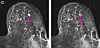

MR-bilde av et bryst med tett brystvev. Den rosa pilen viser en kreftsvulst. Bildet til høyre viser områder i brystet som den kunstige intelligensen har vurdert. Rød betyr høy sannsynlighet for kreft.

Svulster i bryster med tett vev er vanskeligere å oppdage. Kunstig intelligens kan forenkle jobben, viser ny studie.